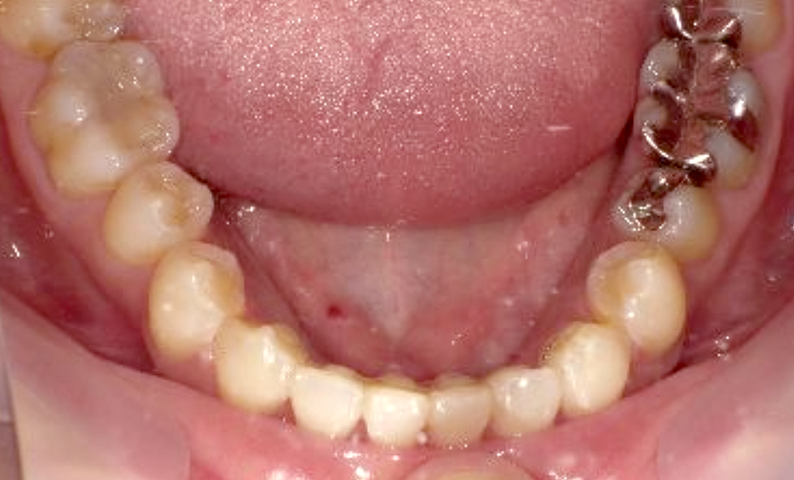

症例_003 下顎だけの部分矯正

治療期間:10ヶ月金額:24万円+税女性前歯のガタガタ下の前歯だけ上顎は補綴治療中

| Before | After |